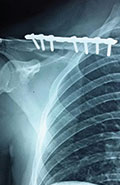

Case 5: Clavicle fracture

Images

X-RAY 1

Displaced fracture right clavicle

Post operative x-ray

Case 6: Clavicle fracture

Displayed Clavicle fracture in a 24 years old cricketer

pre operative X-Ray showing displayed clavicle fracture

post operative x-ray showing fracture fixed with plate and screw